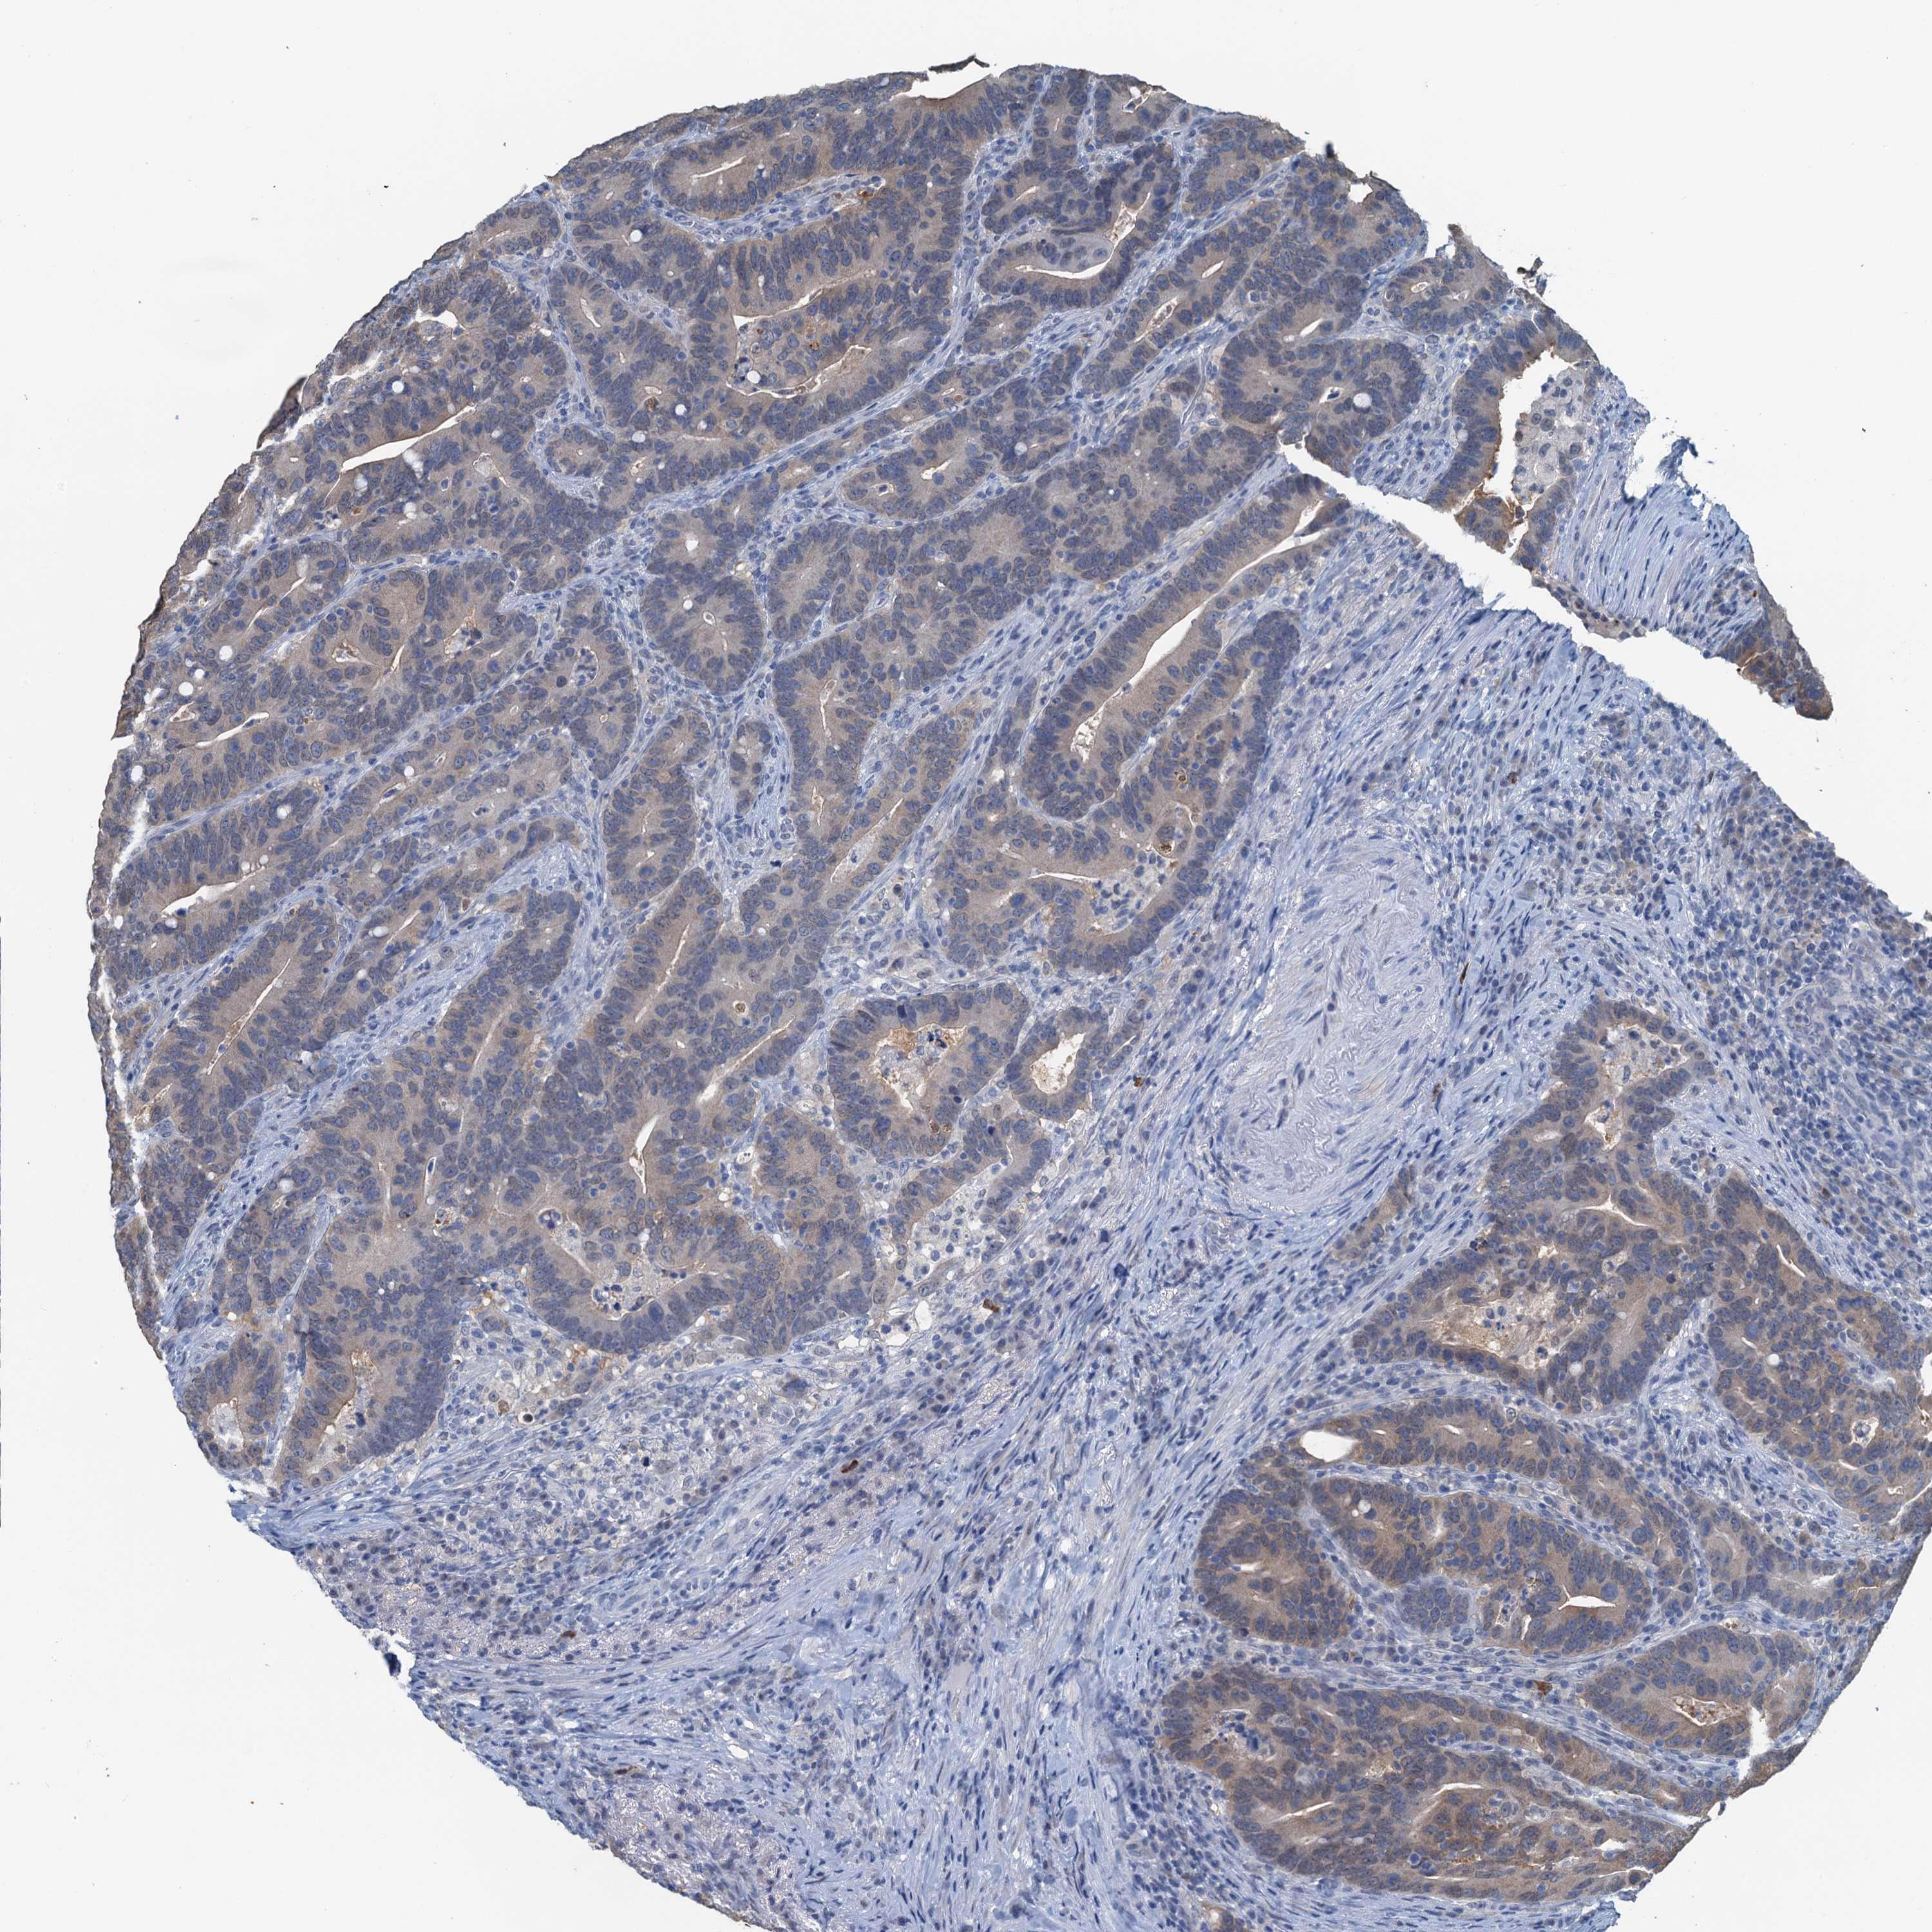

AHCY

CANCER COLORECTAL CANCER Show tissue menu

Colorectal cancer

Human cancer

Colon adenocarcinoma